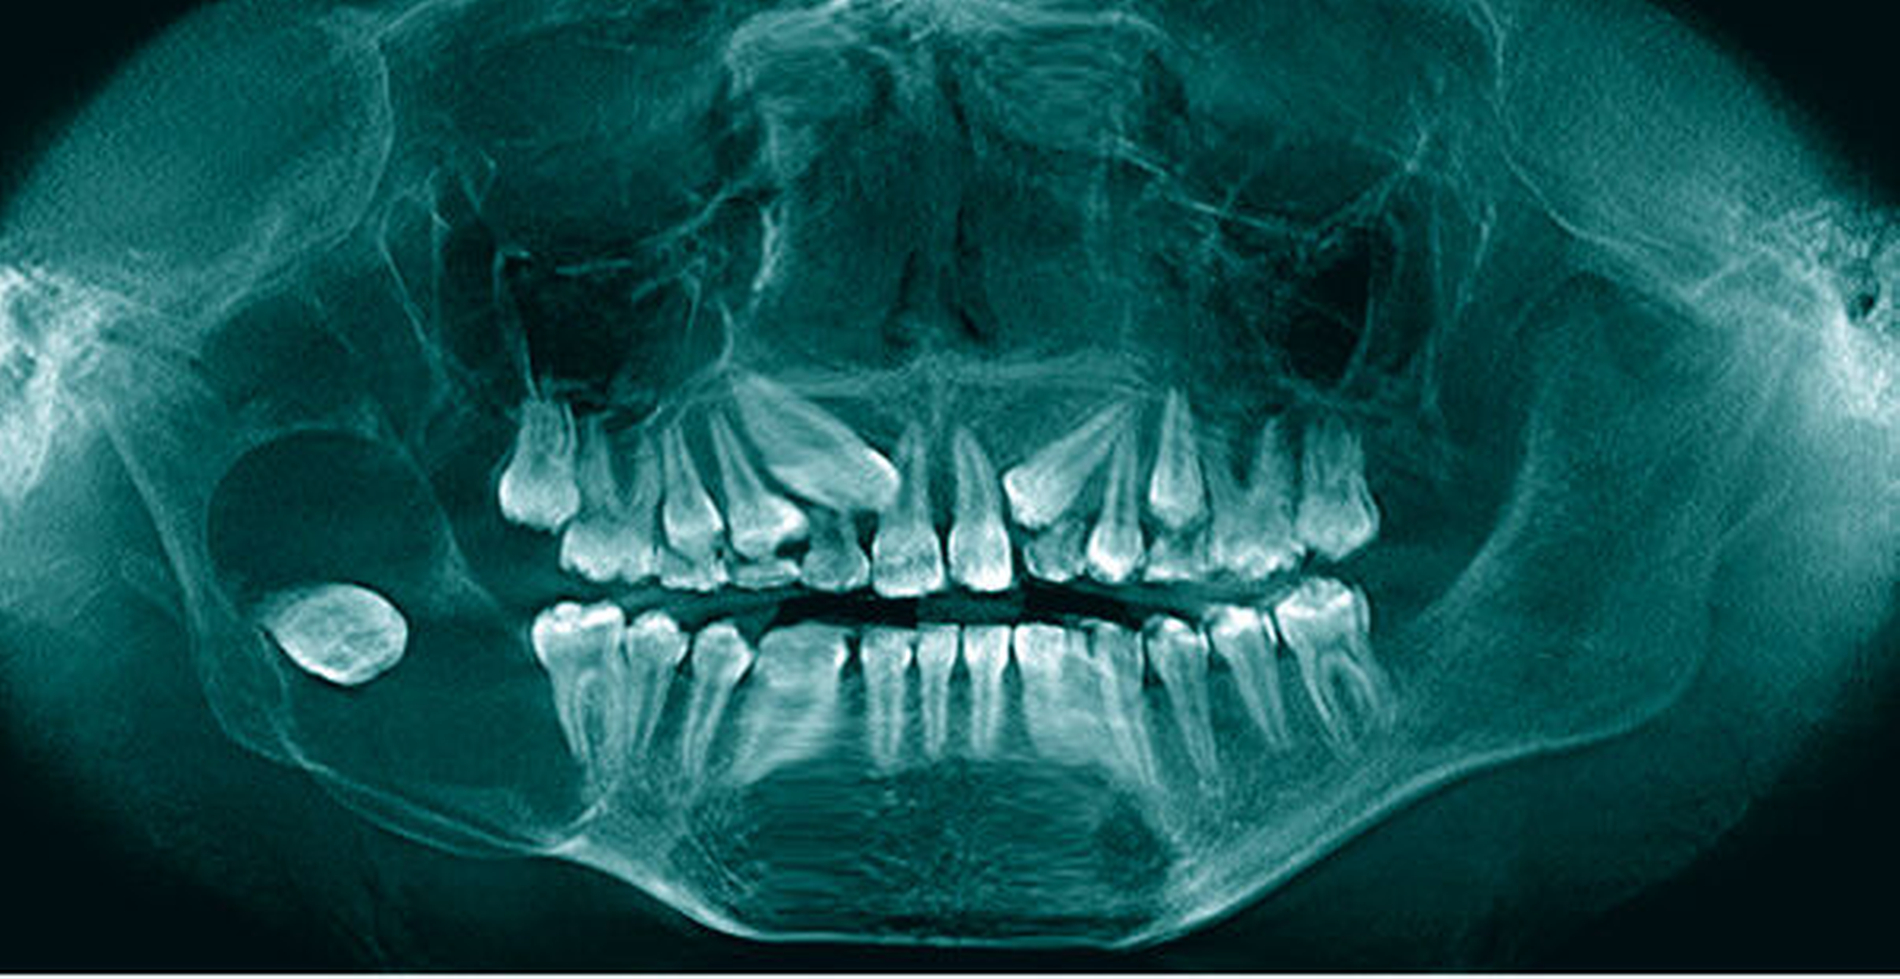

Der oberflächliche Typ des Basalzellkarzinoms ist auch bei der Genodermatose Gorlin-Goltz-Syndrom vertreten, die mit einer Häufigkeit von 1:56.000 gar nicht so selten ist und zur Hälfte der Fälle bei leerer Familienanamnese als Neumutation einzustufen ist. Basalzellkarzinome, meistens vom Rumpfhauttyp, können bei diesem Syndrom schon in Jugendjahren auftreten und haben ansonsten ihren Erkrankungsgipfel im sechsten Lebensjahrzehnt.

Niedergelassenen Zahnärzten, Oral- und MKG-Chirurgen kommt durch die richtige Einschätzung von Keratozysten und die Weiterüberweisung an eine Mund-, Kiefer- und Gesichtschirurgische Klinik häufig ein wichtiger Platz in der Erstdiagnose eines Gorlin-Goltz-Syndroms zu (Abbildung 6). Der zugrundeliegende Gendefekt des autosomal dominant vererbten Leidens ist bekannt und kann in unklaren Fällen in humangenetischen Instituten zum Beweis der Diagnose an einer Blutprobe bestätigt werden. Hier kann der Zahnarzt Leben retten oder frühzeitig einen Patienten vor schweren Operationen bewahren, wenn er beim Auftreten von Keratozysten auf die weiteren Aspekte des Syndroms achtet.

Keratozysten der Kiefer